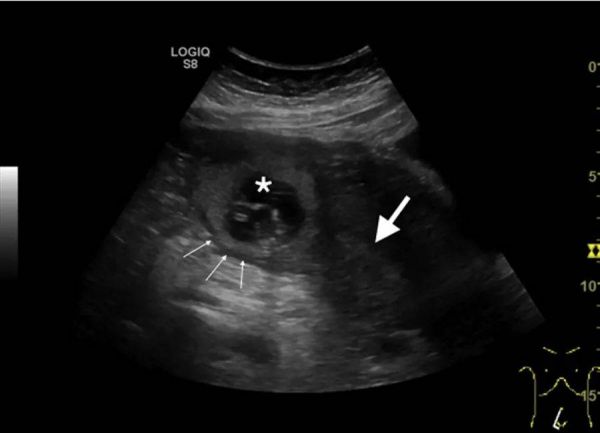

超声显示腹腔内有游离液体,可见偏心妊娠囊,子宫肌层覆盖层薄,子宫内膜腔空虚,间质线征阳性。

图:经腹超声显示胎囊位于子宫底右侧(星号),远离子宫内膜腔(白色大箭头)。图中还显示菲薄肌层(细白色箭头)。

临床诊断:输卵管间质部妊娠。

输卵管间质部妊娠是指植入输卵管间质部分的异位妊娠。输卵管间质部妊娠占所有异位妊娠的2%至3%,但其死亡率是其他输卵管妊娠的2倍以上(2.2%对<1%)。风险因素包括以前的异位妊娠、输卵管手术、体外受精、诱导排卵和性病史。临床症状取决于胎龄。准确诊断仍然有挑战性。超声检查的高灵敏度使其成为诊断输卵管间质部妊娠的最佳一线检查。超声诊断标准包括空虚的子宫内膜腔、偏心的孕囊、薄的或不对称的子宫肌层和阳性的间质线征。